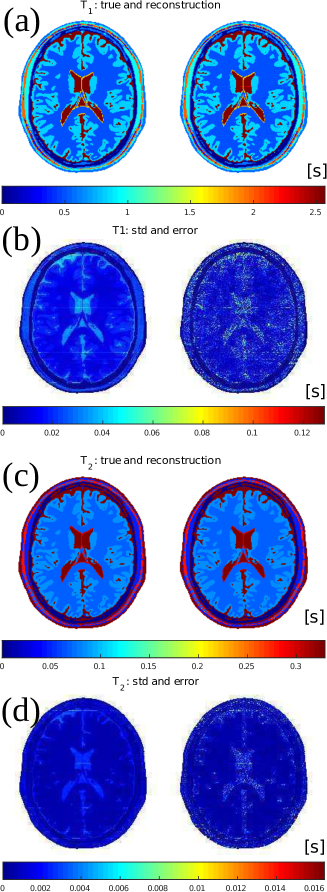

4.2 In-silica high resolution reconstruction

Beside T1subscript𝑇1T_{1}, T2subscript𝑇2T_{2} and ρ𝜌\rho, also the transmit field profile and off-resonance map are reconstructed; they are displayed in Figures 6 and 7. They closely agree with the true values. In Table 2, the mean values and corresponding variations over each tissue type are reported and show high precision.

The root-mean-squared-errors (RMSE) for the B1+superscriptsubscript𝐵1B_{1}^{+} and ω𝜔\omega maps are also very small, namely:

RMSE(|B1+|)=0.0043 [a.u.],RMSE(ω)=0.12 [Hz].formulae-sequenceRMSEsuperscriptsubscript𝐵10.0043 [a.u.]RMSE𝜔0.12 [Hz]\text{RMSE}(|B_{1}^{+}|)=0.0043\text{ [a.u.]},\quad\text{RMSE}(\omega)=0.12\text{ [Hz]}.

The reconstruction time is about 90 minutes. The median number of performed iterations as calculated over all parallel reconstruction processes is 13.

The standard deviations estimated by MR-STAT for T1subscript𝑇1T_{1} and T2subscript𝑇2T_{2} are shown, respectively, in Fig. 6(b) and Fig. 6(d). For comparison, the actual error maps, respectively defined as |T1T1recon|subscript𝑇1superscriptsubscript𝑇1recon|T_{1}-T_{1}^{\mathrm{recon}}| and |T2T2recon|subscript𝑇2superscriptsubscript𝑇2recon|T_{2}-T_{2}^{\mathrm{recon}}|, are also reported and they show clear similarities.

Figure 6: T1subscript𝑇1T_{1} and T2subscript𝑇2T_{2} maps for the synthetic MR-STAT acquisition and reconstruction. (a) and (c): true and reconstructed maps. (b) and (d): standard deviation maps estimated by MR-STAT and the error in the reconstructions (|T1trueT1recon|superscriptsubscript𝑇1truesuperscriptsubscript𝑇1recon|T_{1}^{\text{true}}-T_{1}^{\mathrm{recon}}| and |T2trueT2recon|superscriptsubscript𝑇2truesuperscriptsubscript𝑇2recon|T_{2}^{\text{true}}-T_{2}^{\mathrm{recon}}|).